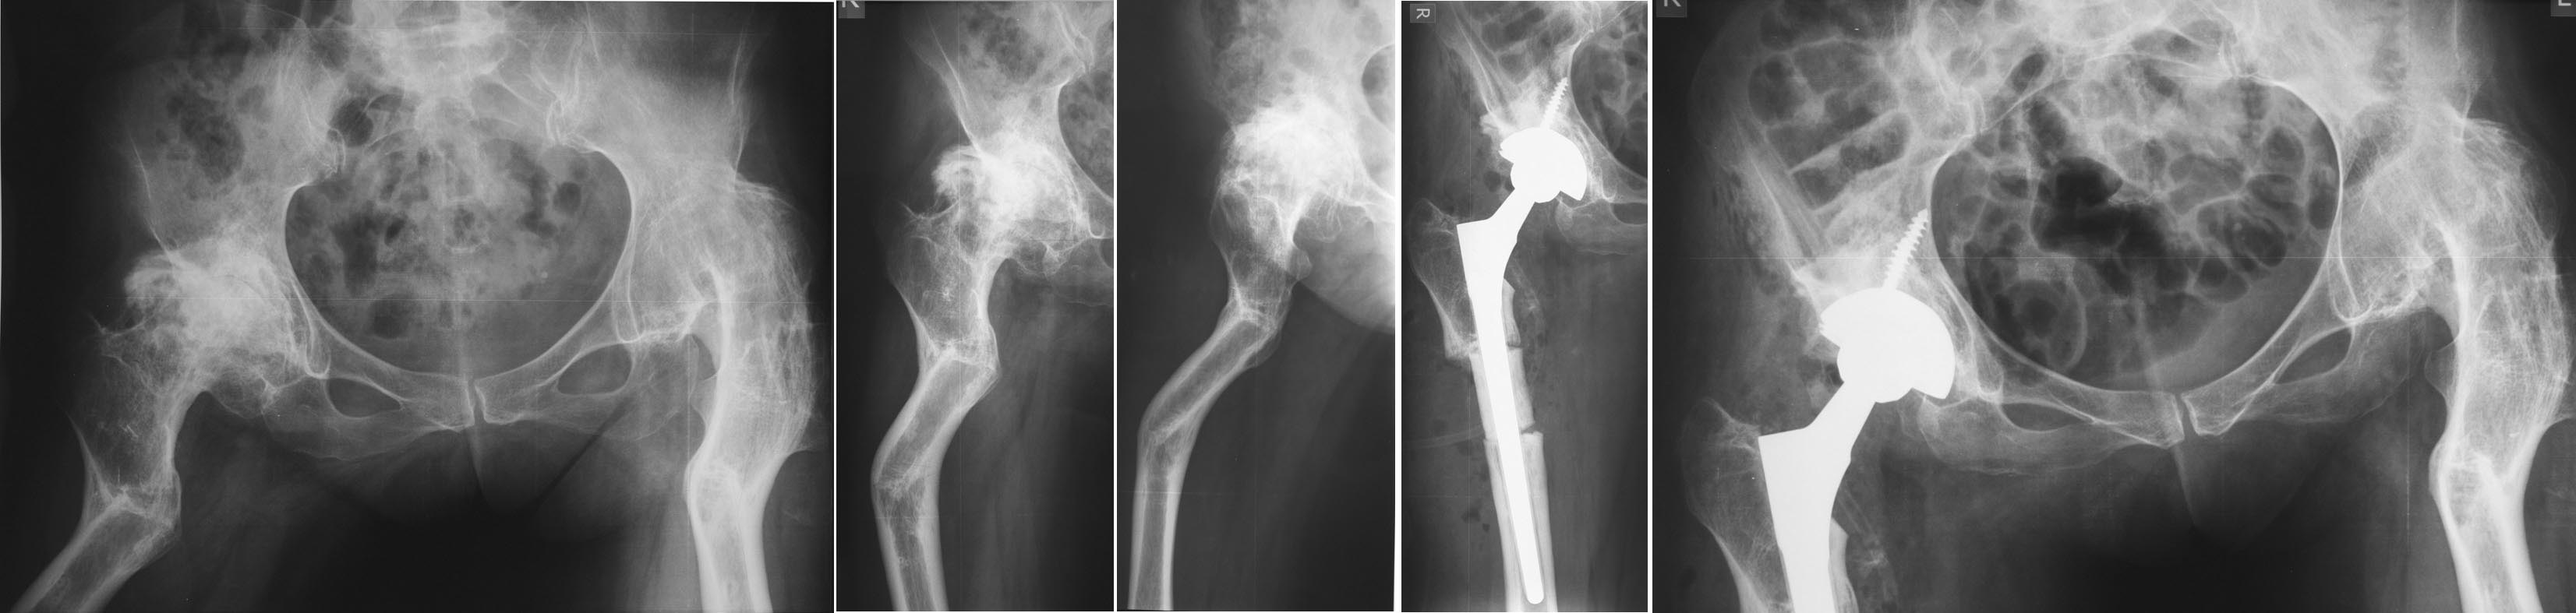

Игорь, на представленных Р-граммах два наблюдения с несколько разным подходом к фиксации большого вертела. В Вашем случае ближе второй вариант, чем-то напоминающий технику Paavilainen'a.